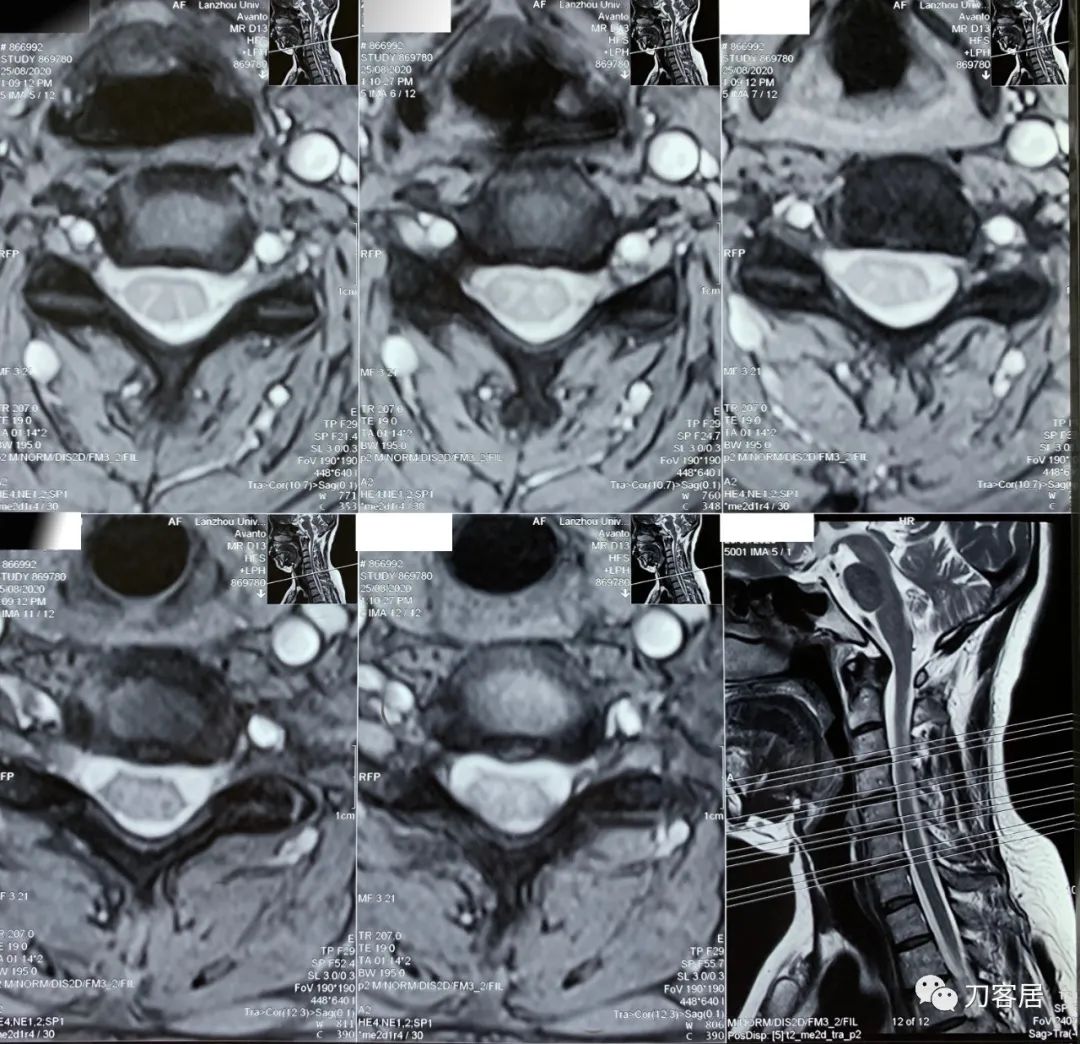

2021年5月17日,西京医院骨科门诊找我就诊,自带影像学检查资料提示腰椎侧弯,腰3-4,腰4-5椎间盘突出,黄韧带肥厚,椎管狭窄。

建议其查双光子骨密度,骨盆正位片以及腰椎间盘平扫。腰椎正侧位X线片以及动力位片,站立位脊柱全长正侧位X线片,以了解其是否有骨质疏松,并了解脊柱侧弯情况,腰椎局部X线表现情况和腰椎间盘突出和椎管狭窄情况。

从这个患者的影像资料分析,颈椎间盘突出问题不大,没有明确的上位神经元损伤表现,所以,不考虑颈椎和胸椎问题。腰椎侧弯畸形,但不严重。因为存在腰椎侧弯,使得腰椎MRI在扫描切面的时候,显示的椎间盘突出或椎管狭窄会有一定的误差,所以,又加做了经椎间盘的CT平扫,影像表现并不严重,综上,腰椎间盘突出,腰椎管狭窄,腰椎侧弯,不考虑手术治疗。同时,患者的主要痛苦是心理疾病,而不是器质性疾病,所以,以心身疾病治疗为主。虽然患者骨密度检查结果提示正常,但X线片显示骨质疏松,且其症状也与骨质疏松的症状有符合之处,比如静息痛,不能入睡,动作及姿势变换时痛加重等,所以,给予实验性抗骨质疏松治疗,以观疗效。